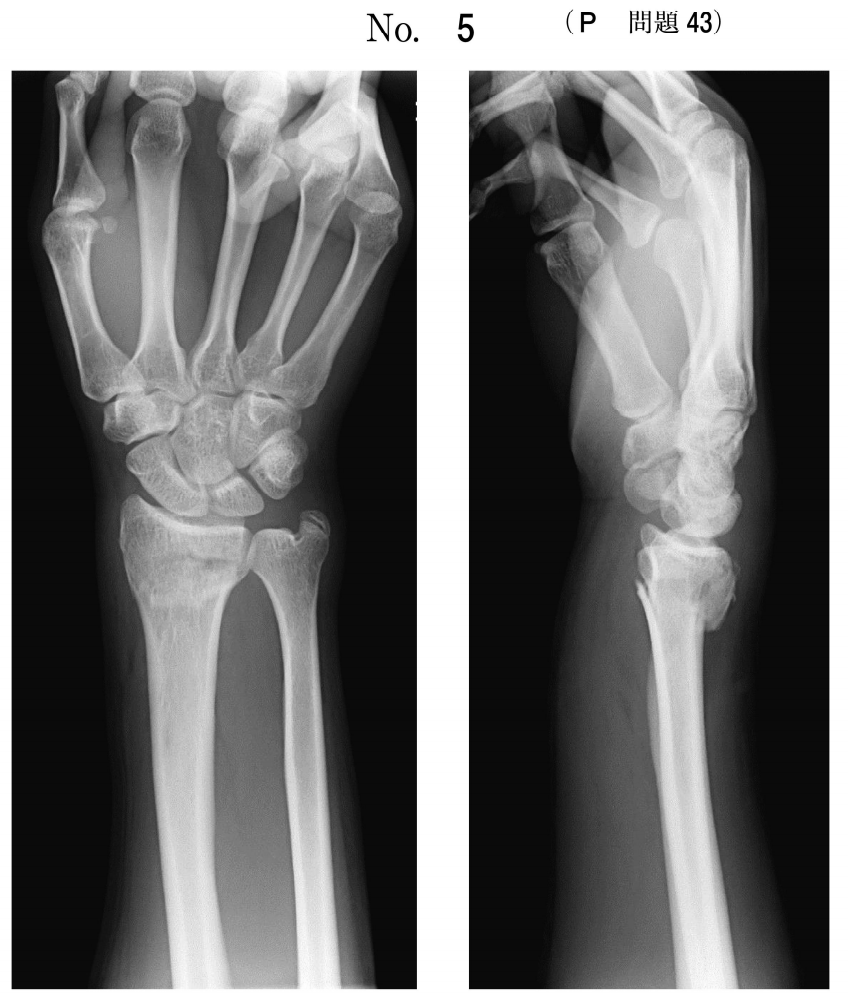

トップ 医療・介護・福祉に関する資格 理学療法士 平成30年度 第53回 過去問(2018年度) 問43 全部で158問 挑戦中 午前 問題 手関節背屈位で手をついて転倒した患者の工ックス線単純写真(別冊No.5)を別に示す。 この病態として正しいのはどれか。 (1) chauffeur’s骨折 Calles骨折 Galeazzi骨折 Monteggia骨折 Smith骨折 次の問題へ